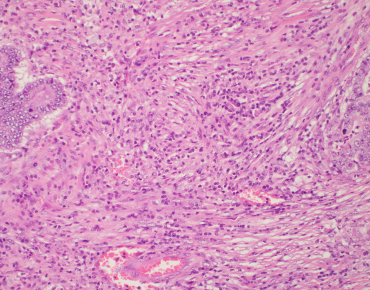

International Immuno-Oncology Biomarker Working Group on Breast Cancer

Over the past few years, Roberto Salgado, Sherene Loi and Carsten Denkert have developed the International Immuno-Oncology Biomarker Working Group on Breast Cancer, with members including expert clinical research groups, pathologists, clinicians and statisticians worldwide currently knowledgeable in the field of Immune-oncology Biomarkers. The purpose of this Working Group is to develop, in a timely manner, standards on the assessment of Immuno-Oncology Biomarkers to aid pathologists, clinicians and researchers in their research and daily practice.